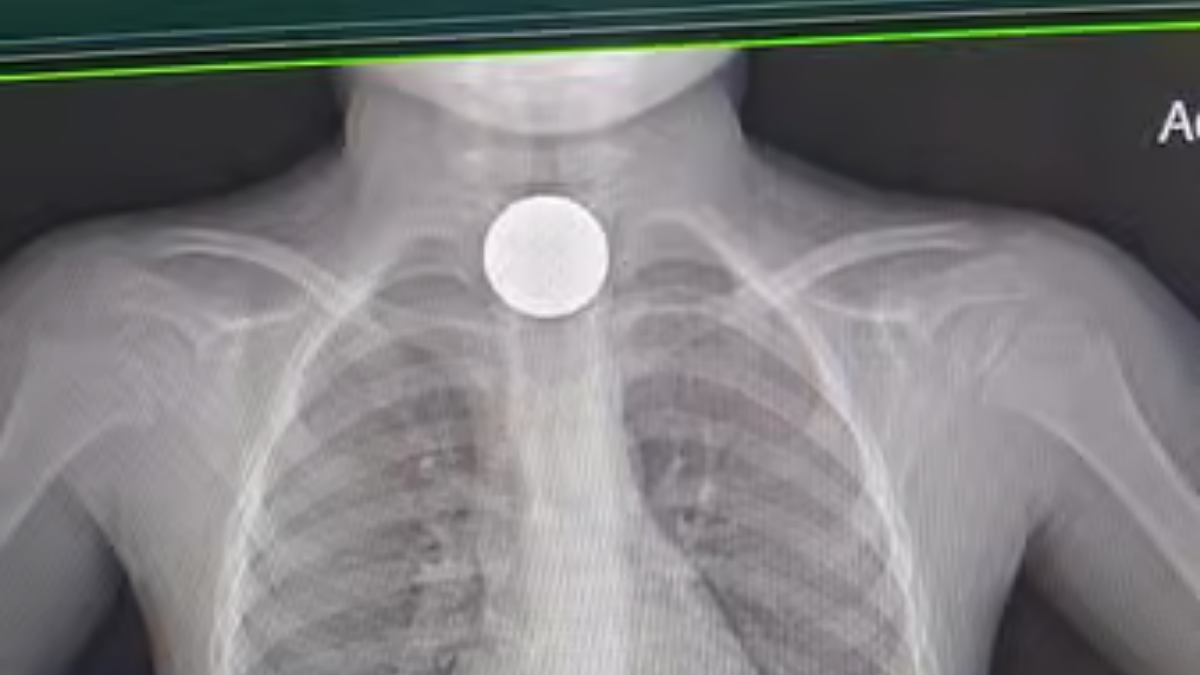

A four-year-old boy is recovering after doctors at a Dubai hospital extracted a coin lodged in his oesophagus during an emergency procedure that took just two minutes to complete.

Muhammad Shahzain Awan was rushed to Medcare Royal Speciality Hospital in Al Qusais after his parents noticed he was vomiting and struggling to breathe. The coin had become stuck in the upper oesophagus — a location where even minor movement carries the risk of serious complications.

Physicians performed an emergency endoscopic procedure, using a minimally invasive approach to retrieve the object. The child was stabilised shortly after and later discharged following a period of observation.